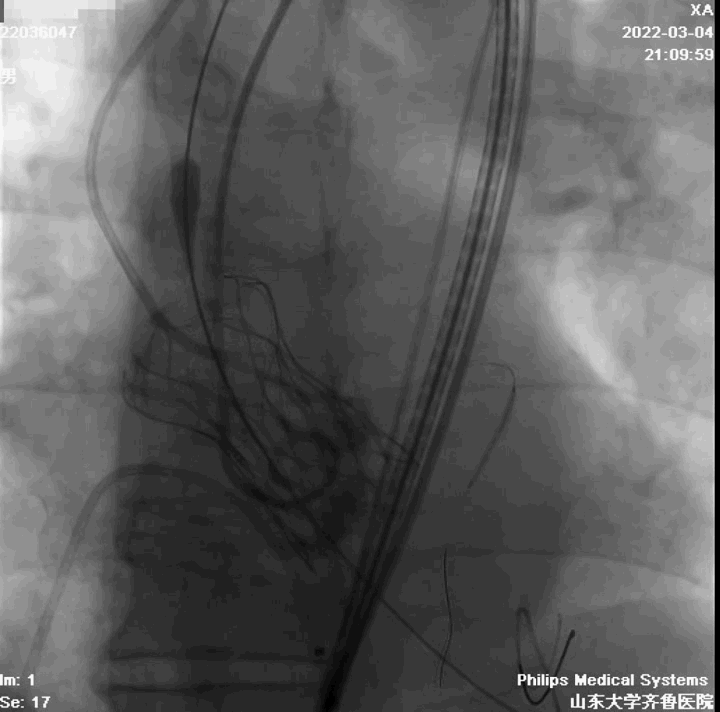

左冠造影

右冠造影

主动脉根部造影

球囊扩张

左冠球囊保护

定位

起始缓慢释放

造影观察

瓣膜工作,造影观察

完全释放

造影

球囊后扩

最终结果